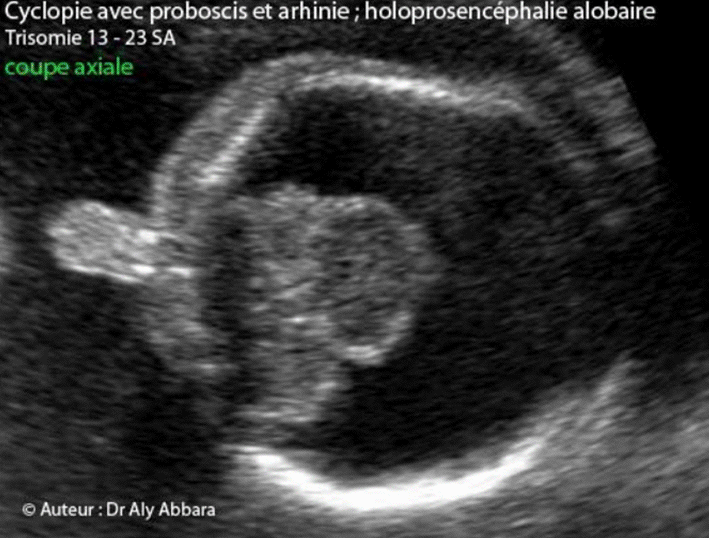

Holoprosencéphalie

C'est une sévère anomalie cérébrale due à un arrêt précoce du clivage et de la rotation du cerveau antérieur.

L'holoprosencéphalie est une anomalie d'une faible fréquence à la naissance (1:16 000 accouchements), mais elle est mise en évidence chez (1:250) fœtus avec sex-ratio = (M:F = 1:3) pour la forme alobaire et (1:1) pour la forme lobaire.

Les anomalies chromosomiques dans lesquelles l'holoprosencéphalie a été observée sont : la trisomie 13, la trisomie 18 et la monosomie 21. Des cas sporadiques avec caryotype normal ont été rapportés.

- 1- Holoprosencéphalie

alobaire (alobar holoprosencephaly) :

- absence de clivage longitudinal des deux

hémisphères cérébraux, donc :

- le sillon interhémisphérique dorsal est absent ;

- le sillon interhémisphérique sur la face ventrale des pôles frontaux est absent aussi (premier dénominateur commun des holoprosencéphalies) ;

- la fusion

ventriculaire prend la forme d'une cavité ventriculaire

unique

en avant comme en arrière du cerveau (monoventricule) ; ce monoventricule peut évoluer vers la partie dorsale apicale du cerveau sous forme de sac (sac dorsal) écrasant le parenchyme cérébral périphérique avoisinant ;

- le parenchyme cérébral

en avant est très réduit aussi ;

- les noyaux gris sont

fusionnés : fusion complète des thalamus avec absence du 3ème ventricule

- agénésie du corps calleux

- absence du cavum du septum pellucidum (deuxième dénominateur commun des holoprosencéphalies)

- les nerfs optiques sont présents ou fusionnés en un nerf optique unique ;

- les tractus olfactifs sont absents (ou fusionnés en un tractus olfactif unique).

- l'atrésie de l'aqueduc de Sylvius quand elle est associée à l'holoprosencéphalie alobaire, elle est à l'origine de la dilatation du ventricule cérébral unique (hydrocéphalie).

- Le cervelet est habituellement présent.

- Les signes permettant le diagnostic au cours de échographie anténatale :

- Au premier trimestre de la grossesse :

On peut observer la présence d'un seul ventricule, puis l'apparence anormale des plexus choroïdes (les deux plexus choroïdes normaux composent ensemble une forme ressemblant à un papillon "signe du papillon - Butterfly sign" ) ; ce signe est absent dans l'holoprosencéphalie alobaire.

- Au deuxième trimestre de la grossesse :

monoventricule prenant un aspect kystique (sac dorsal) ;

fusion des thalami et absence des structures médianes (faux du cerveau, cavum du septum pellucidum, corps calleux et troisième ventricule) ;

microcéphalie ou macrocéphalie (si hydrocéphalie associée par la sténose de l'aqueduc de Sylvius) ;

puis dans 72 % des cas, les anomalies sévères de la face ( , ) sont habituellement présentes dans l'holoprosencéphalie alobaire (cyclopie, proboscis, hypotélorisme, si deux yeux sont présents comme c'est le cas dans éthmocéphalie, la cébocéphalie, et les fentes labiopalatines médianes).

- 1 - Cyclopie (monophtalmie,

arhinie, proboscis et cerveau

alobaire).